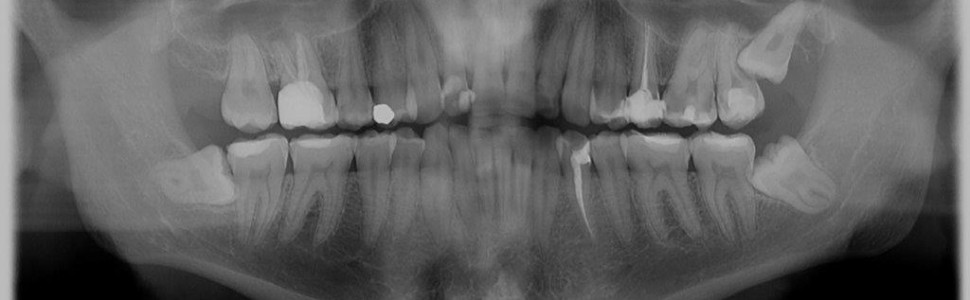

Diagnostyka resorpcji zewnętrznej drugiego zęba trzonowego wywołanej mezjalnokątowo zatrzymanym trzecim zębem trzonowym

Dolne, jak i górne trzecie zęby trzonowe są zębami, które najczęściej ulegają zatrzymaniu. Podjęcie decyzji o ekstrakcji bezobjawowego trzeciego zęba trzonowego może sprawiać trudności. Powszechnie wykonywane zdjęcie pantomograficzne może nie ujawniać toczącej się resorpcji zewnętrznej korzenia zęba siódmego. Celem pracy jest przedstawienie na podstawie piśmiennictwa i opisów przypadków diagnostyki radiologicznej resorpcji zewnętrznej zęba trzonowego, spowodowanej przez zatrzymanego bezobjawowego zęba trzeciego trzonowego.

Maxillar and mandibular third molars are the teeth that are the most often impacted. Decision regarding extraction of asymptomatic impacted third molar is sometimes difficult. Acommon pantomographic radiograph may not reveal the ongoing external root resorption of the second molar. The aim of the present study was to assess the incidence and risk factors of external root resorption in second molars with mesially and horizontally impacted mandibular third molars, determining treatment procedure and showing our own cases.